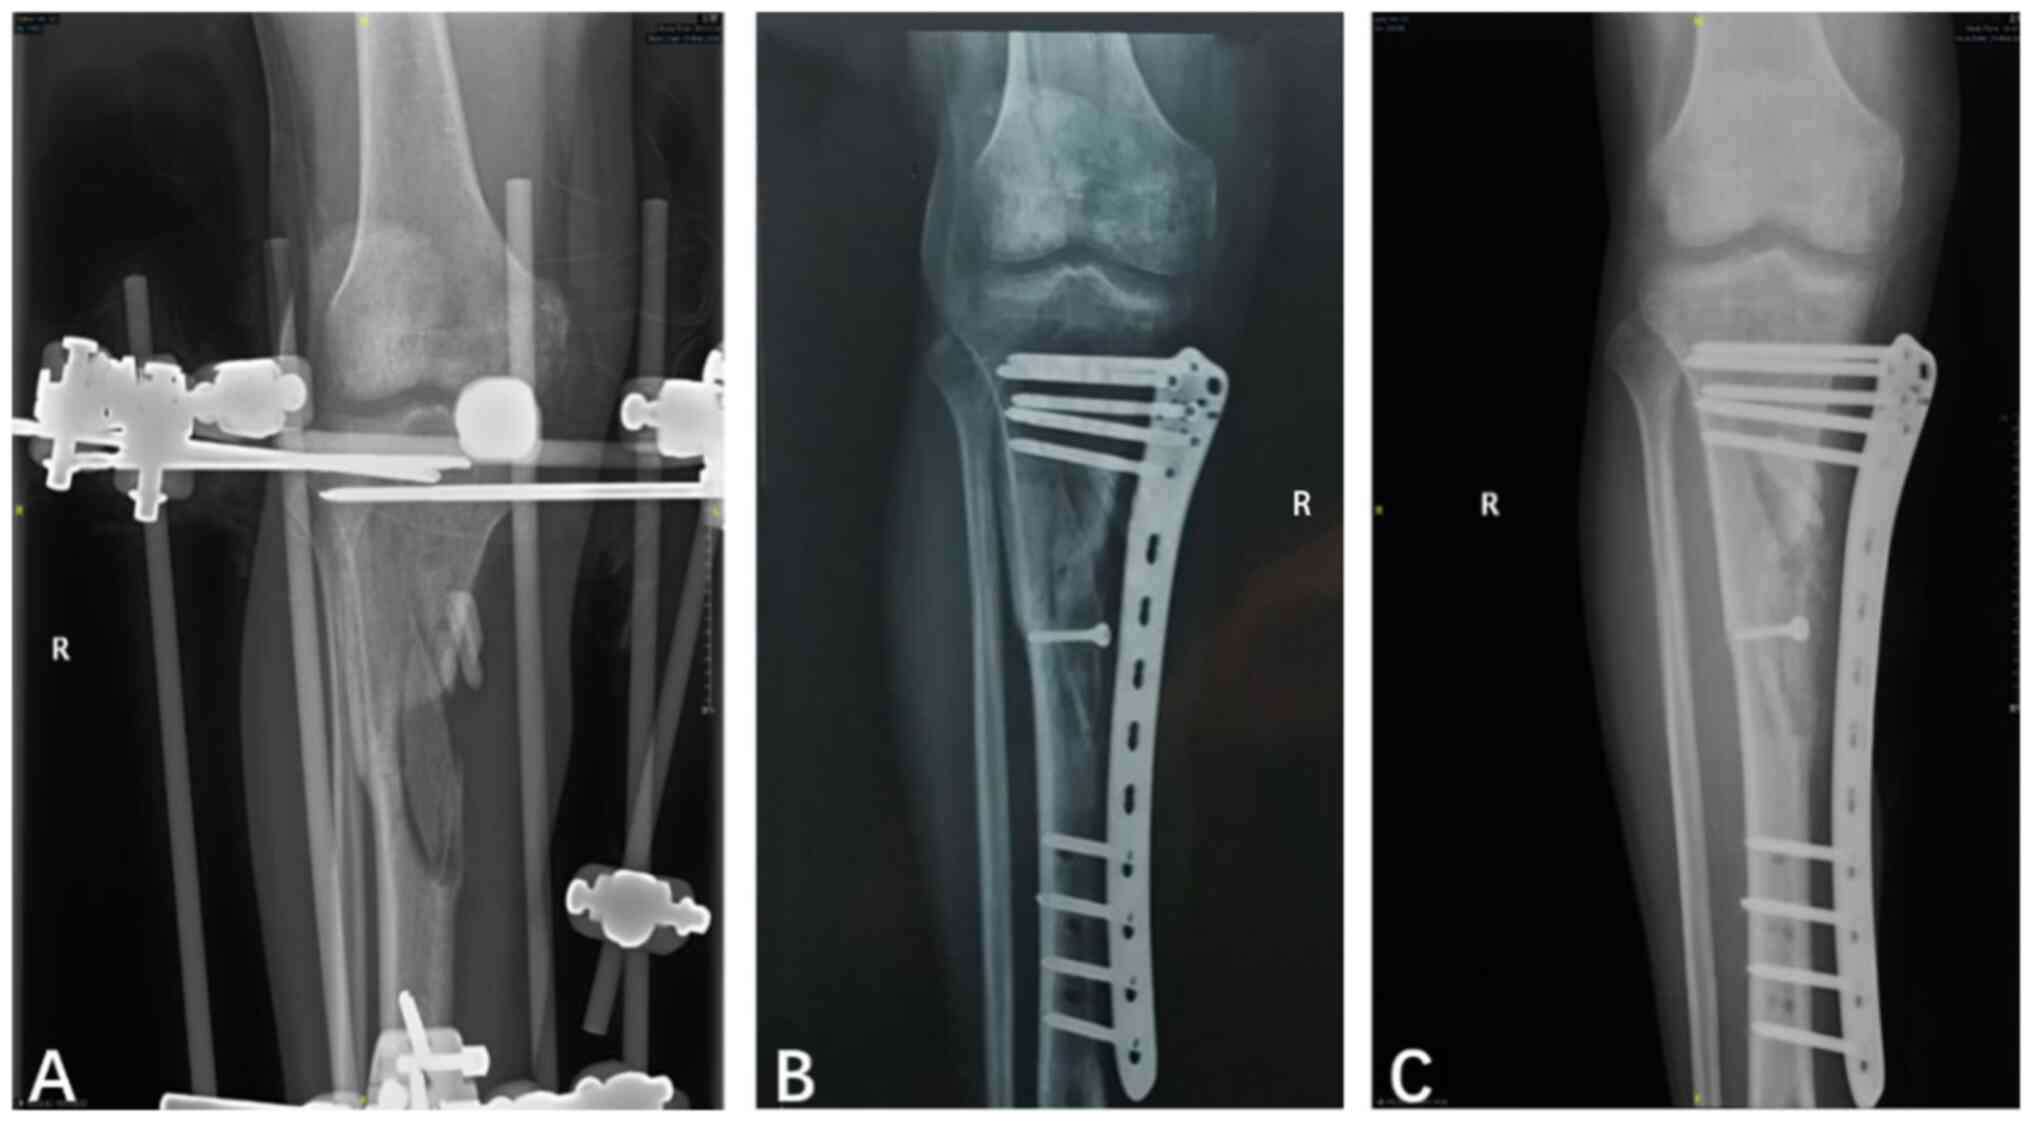

In the EX group during follow-up, 20 patients (90.9%) showed evidence of bone healing and had a median time to union of 13.1 months (Table I). However, 3 patients (13.6%) in this group had infection recurrence, which exhibited as oozing pus in wounds and elevated inflammatory cytokine levels. Also, 5 patients (22.7%) had pin-tract infections, 2 patients (9.1%) had non-union after 12 months of follow-up, and 3 patients (13.6%) had loosened pins (Table I). In addition, 8 patients had shortened limbs and deformed tibia. A total of 5 out of 8 patients had malformations causing limb shortening, with a mean postoperative limb shortening length of 3.2 cm (IQR, 1.5-6 cm). Of these patients, 3 patients also presented with tibial deformity. One patient with limb shortening of 6 cm underwent the Ilizarov procedure, while the other 4 patients did not undergo surgery. The other 3 patients exhibited only tibial deformity. All 6 patients with deformity, including 3 patients with concurrent shortened limbs, had varus or valgus malalignment >2˚. One of these 6 patients had a distal tibial recurvatum of 11˚ but underwent no further surgery. The proportion of cases with satisfactory functional status, which was assessed based on the scores for knee and ankle joint functions of the affected lower limb, were 81.8% before surgery and 86.4% after surgery (Table III). Representative follow-up X-ray images of patients who underwent bone grafting with retained unilateral external fixation are shown in Fig. 1.

Figure 1

Representative X-rays of a patient (no. 6) who underwent bone grafting with retained unilateral external fixation. (A) Cement spacer placed in the bone defect using unilateral external fixation to maintain tibial stability before the second-stage surgery. (B) Bone defect filled with autogenous iliac bone grafts and callus formation 3 months after the second-stage surgery with external fixation. (C) Increased callus volume 1 year after the second-stage surgery. R, right.